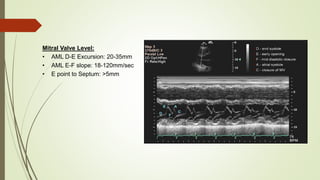

Mitral Valve Level:

• AML D-E Excursion: 20-35mm

• AML E-F slope: 18-120mm/sec

• E point to Septum: >5mm